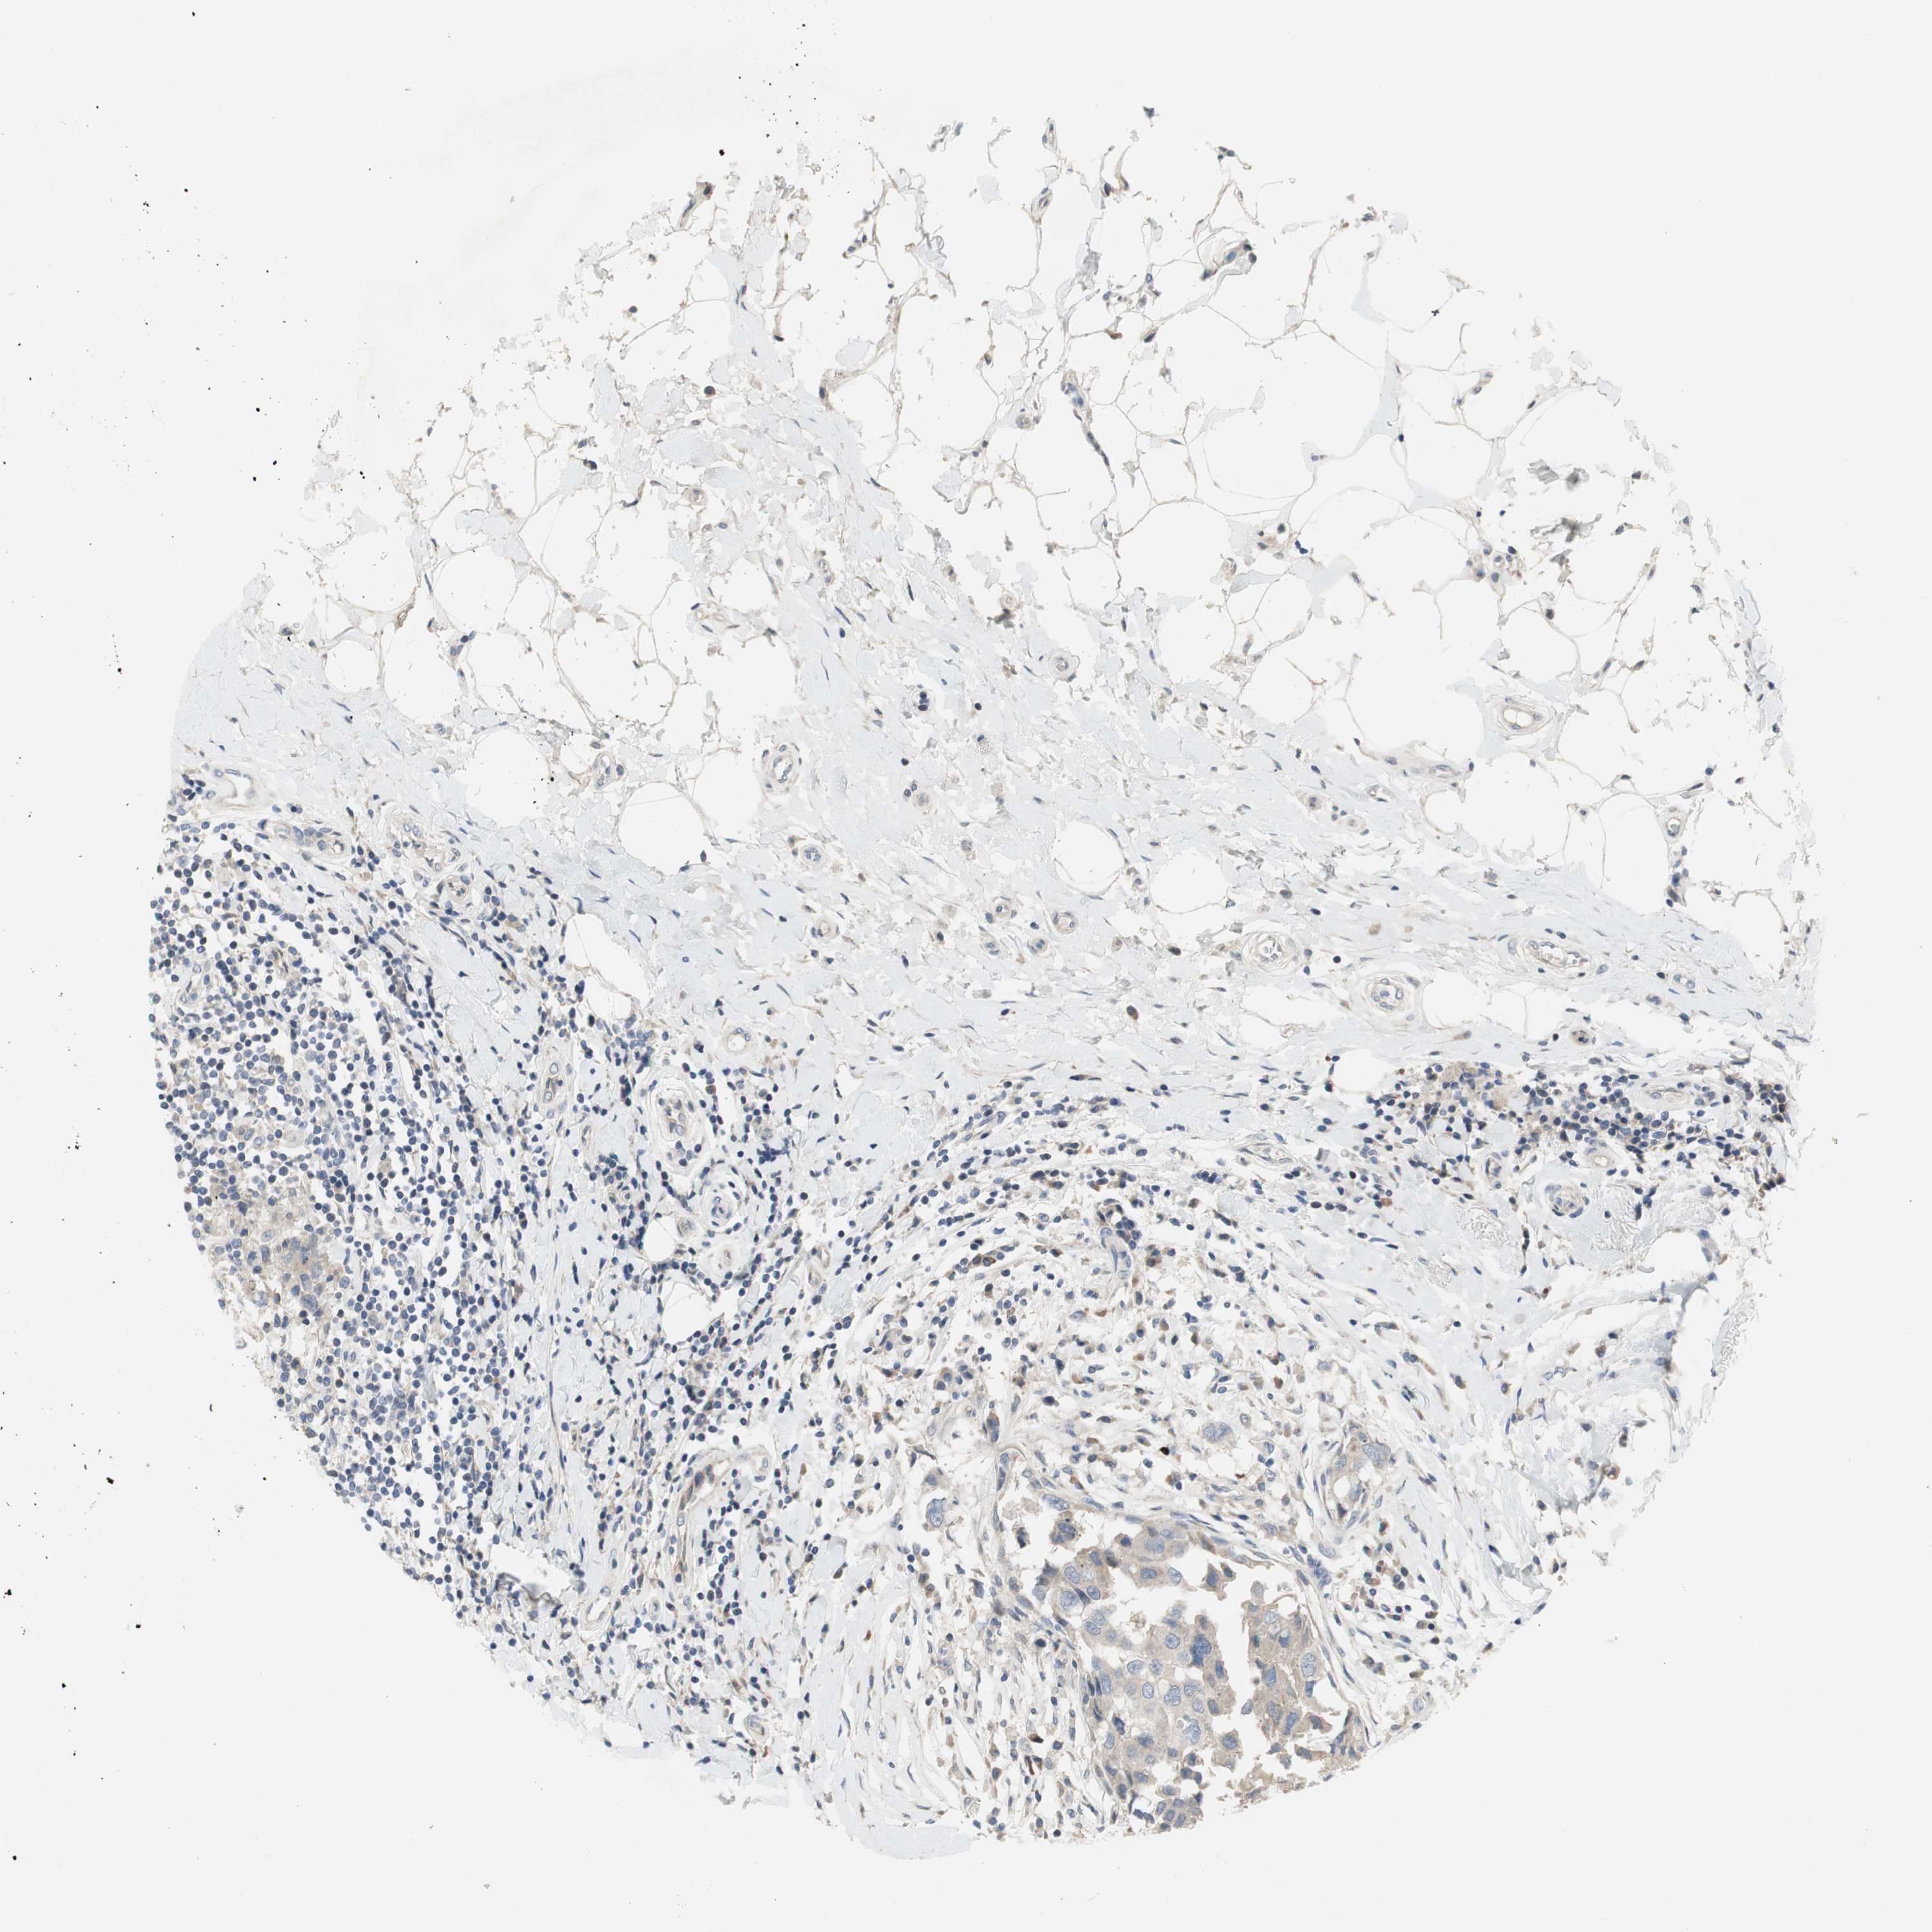

CANCER BREAST CANCER Show tissue menu

BRCA TCGA BRCA VALIDATION PROTEIN EXPRESSION